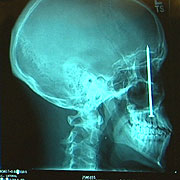

Construction worker Patrick Lawler thought he had a toothache. He tried painkillers and ice packs but received no relief. Finally he went to the dental office where his wife worked and the x-ray revealed the problem: he had a four-inch nail in his head. Apparently six days earlier Patrick’s nail gun misfired and one of the nails shot into his mouth and embedded itself in his head, narrowly missing his right eye.

After a four-hour surgery to remove the nail, a neurologist admitted that it was a “pretty rare injury…but this is the second one we’ve seen in this hospital where the person was injured by the nail gun and didn’t actually realize that the nail had been embedded in his skull.”